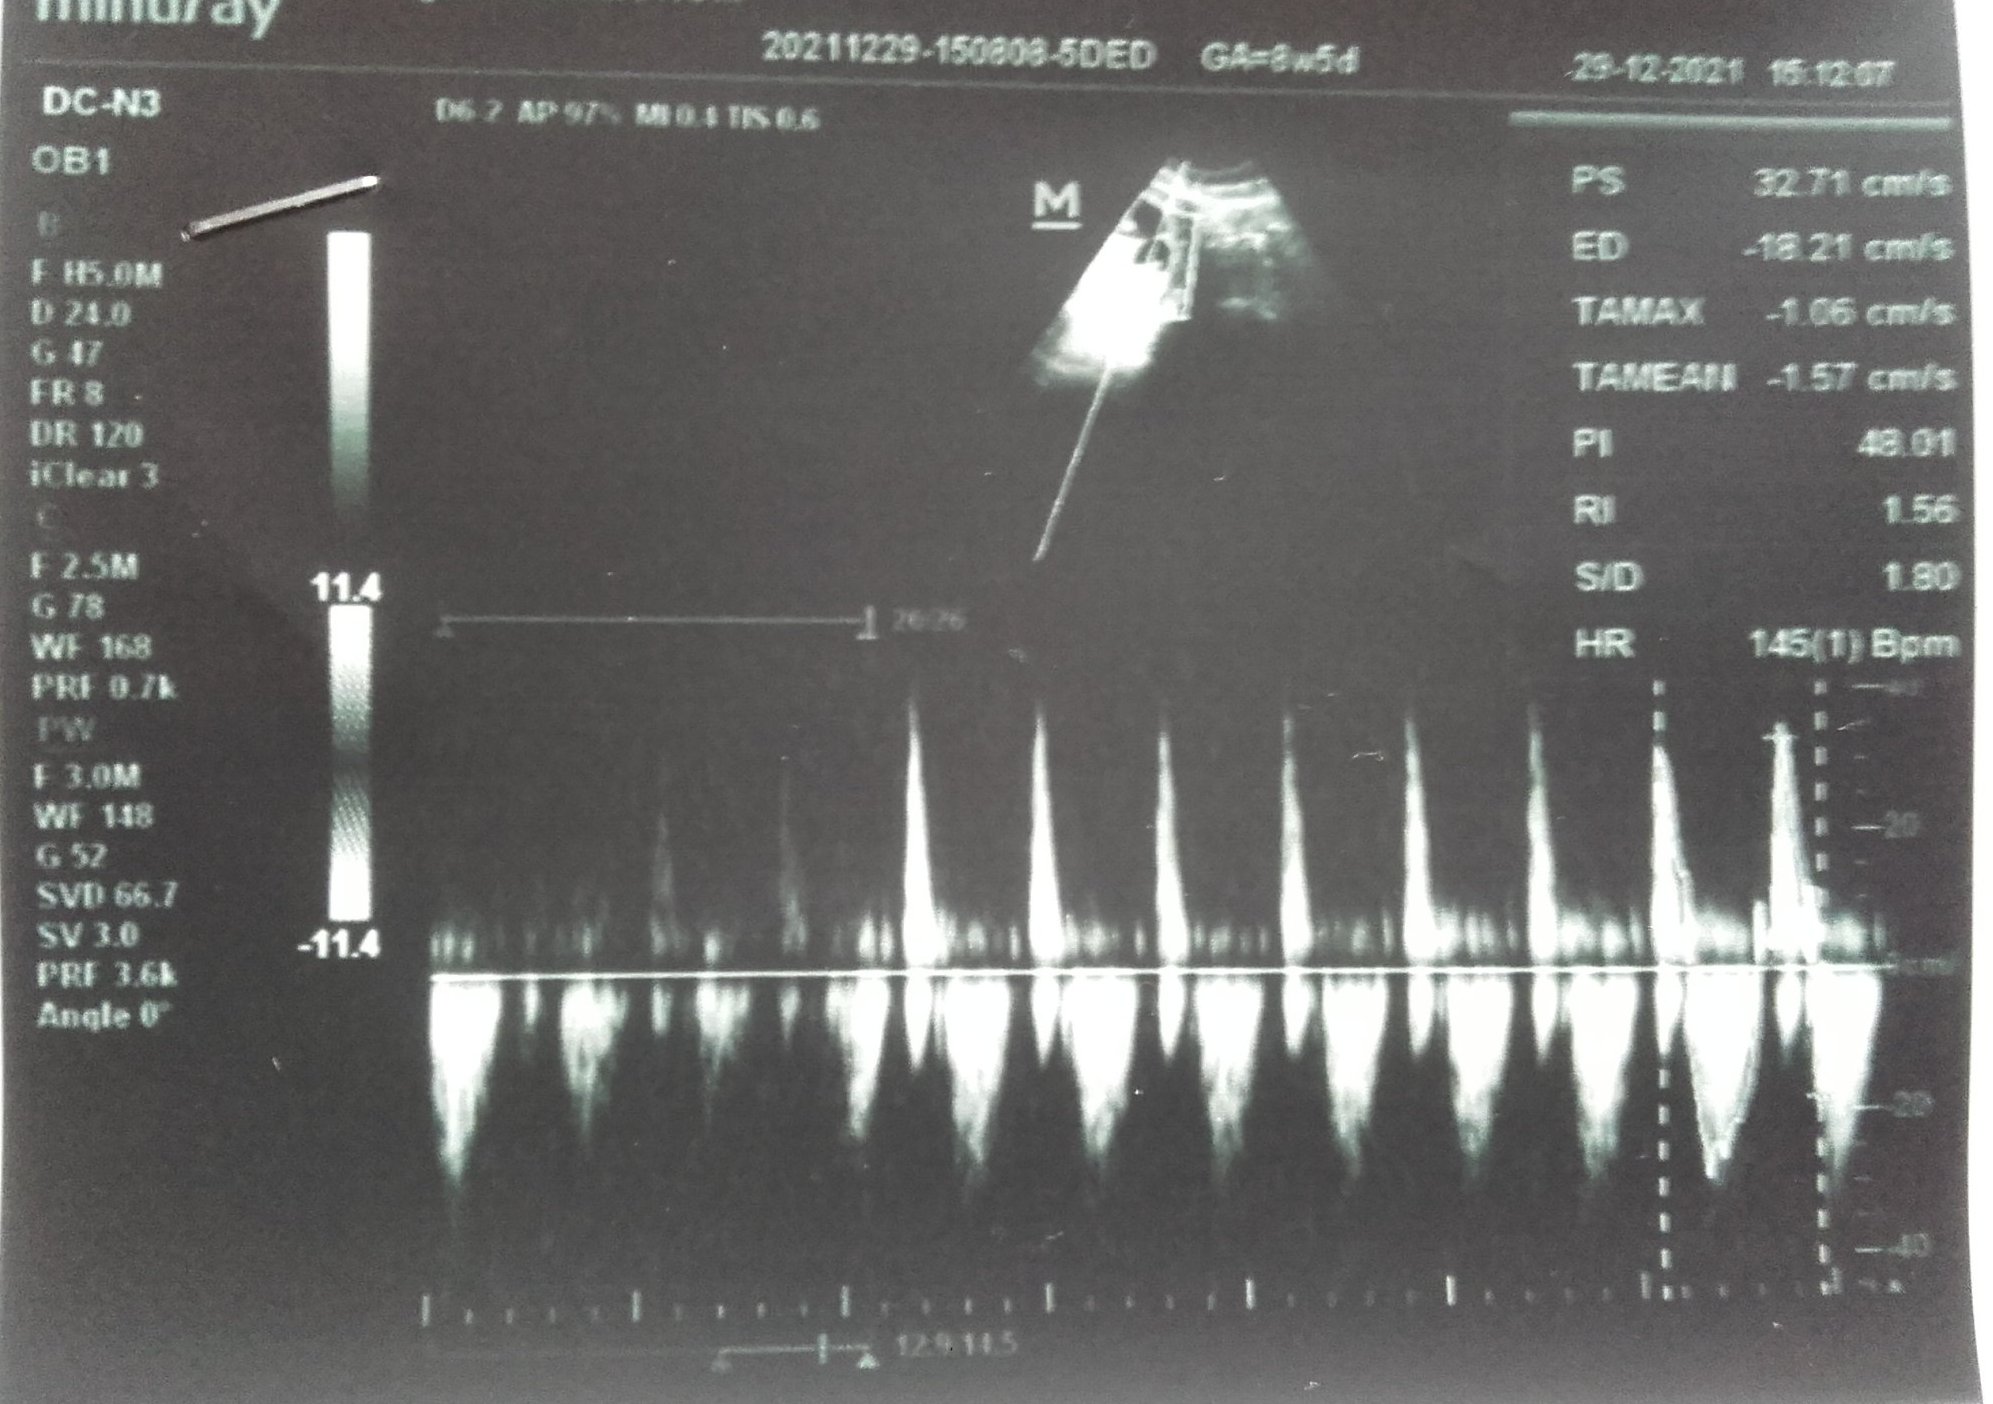

Как се наблюдава както тромбофилията, така и кръвният поток по време на бременност?